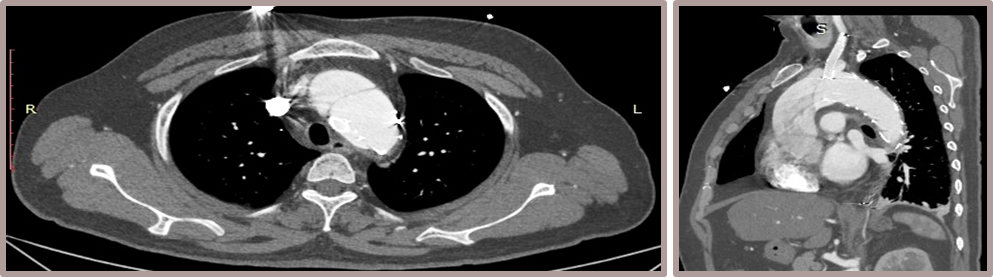

★ Case 2

男性,50岁,胸痛7+小时;

既往史:既往诊断高血压,未规律服药及监测血压;

个人史:吸烟30余年,日均20支;

夹层动脉瘤CTA:A型主动脉夹层,初破口位于主动脉弓近端,逆撕至主动脉根部,左颈总动脉及左锁骨下动脉根部受累,夹层远端累及至双侧髂动脉。

术前影像

置入双分支术中支架

术后影像